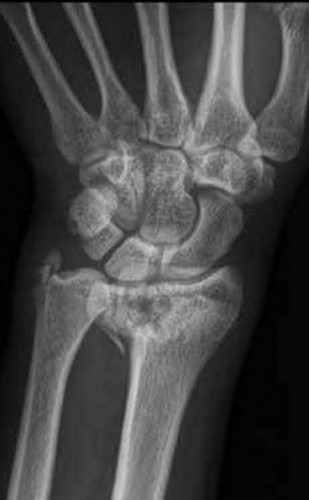

A 22-year-old male falls onto an outstretched hand and sustains a displaced fracture through the proximal pole of the scaphoid. Avascular necrosis of the proximal pole is highly likely due to the disruption of its primary vascular supply. Which vessel provides this critical retrograde perfusion?

The primary blood supply to the scaphoid is from the dorsal carpal branch of the radial artery, which enters the dorsal ridge of the scaphoid at the waist and courses proximally. This retrograde blood flow makes proximal pole fractures highly susceptible to avascular necrosis and nonunion. The superficial palmar branch provides a minor supply (about 20%) to the distal pole.